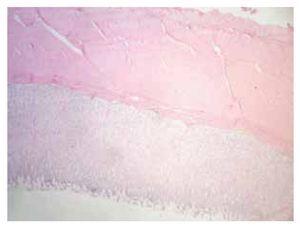

Descripción microscópica: cambios histológicos observados en la región fúndica y antral del modelo porcino a las 24 horas y a los tres días postinyección endoscópica de cinco soluciones (Figuras 1 y 2).

Figura 2. Cuadrante con metilcelulosa. Presencia de focos de inflamación granulomatosa a nivel submucoso.